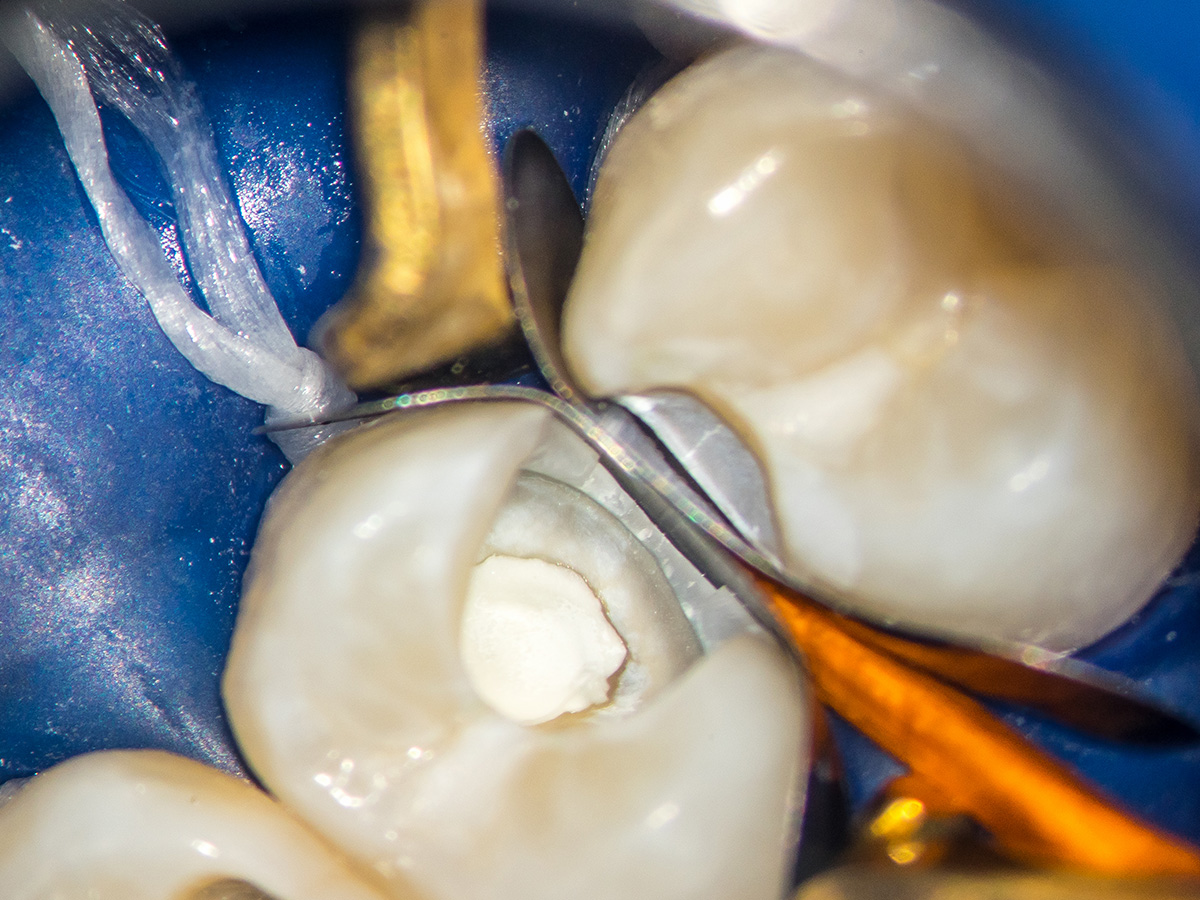

Eine 16-jährige Patientin erschien mit einer ausgeprägten CP bei reversibler Pulpitits in unserer Praxis. Nach einem Aufklärungsgespräch haben wir uns für eine partielle Pulpotomie mit Bioceramics-Abdeckung und ACTIVA-Deckfüllung entschieden. Die Bildreihe zeigt das Vorgehen, das Recall-Bild der Füllung ist fünf Monate alt.

Abbildung 3

Grobe Umrissform. Eröffnung der Kavität an 24.